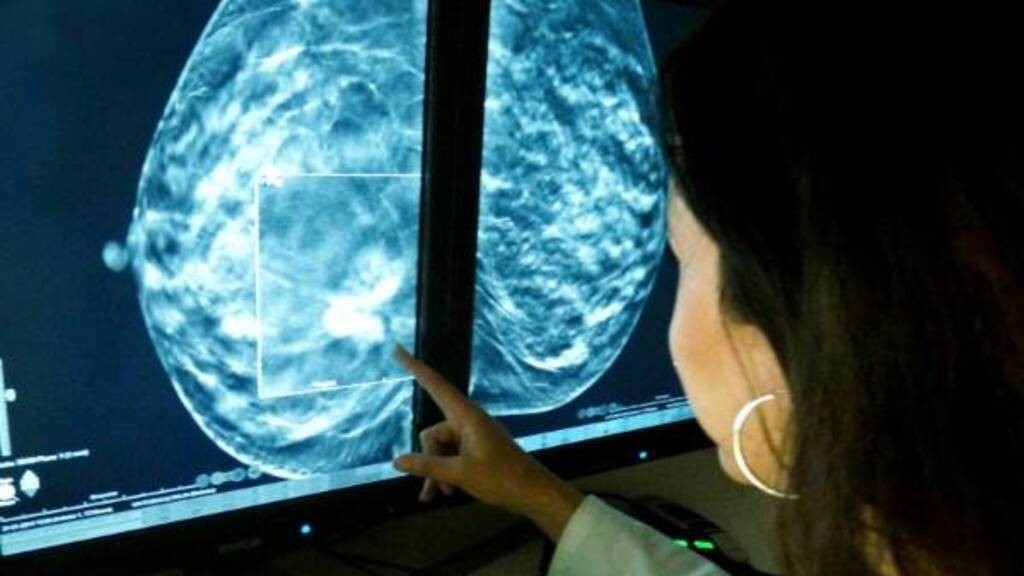

Cáncer de mama: la importancia de las mamografías

- La mamografía es una herramienta fundamental para la detección temprana del cáncer de mama porque permite identificar tumores o anomalías antes de que aparezcan síntomas visibles.

- Detectar el cáncer en una etapa temprana mejora significativamente las posibilidades de tratamiento exitoso y reduce la mortalidad, con estudios que estiman una disminución del 20% al 40% en las muertes por esta enfermedad.

- Al diagnosticar el cáncer precozmente, se pueden aplicar tratamientos menos agresivos, como cirugías conservadoras y terapias con menos efectos secundarios.

- La detección temprana también implica un menor costo económico y emocional, ya que los tratamientos son más sencillos, menos prolongados y con mejores resultados.

- Es un estudio rápido, no invasivo y accesible, con campañas gratuitas o de bajo costo disponibles en muchos sistemas de salud pública.

- Se recomienda realizar una mamografía cada 1 o 2 años en mujeres entre 50 y 69 años, aunque también puede indicarse antes en mujeres con antecedentes familiares u otros factores de riesgo.

- Si bien la mamografía no previene el cáncer, sí puede salvar vidas al detectarlo de forma temprana, siendo una herramienta clave en la medicina preventiva y el cuidado de la salud femenina.